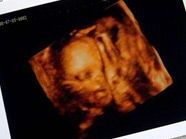

Bei dem Phänomen, das Mediziner “foetus in foeto” nennen, wachsen zunächst zwei Kinder im Mutterleib heran, bis sich der eine Fötus den anderen einverleibt. Der Zwilling könne eine Bedrohung für Meng Ru werden, wenn er nicht bald entfernt werde, sagten die untersuchenden Klinikärzte in Luohe.

Meng Rus Körper begann wenige Monate nach der Adoption durch ein Paar in Luohe in der Provinz Henan zu schwellen. Der Adoptivvater Kang Xi brachte Meng Ru in eine Klinik, wo der Zwilling entdeckt wurde. Angesichts der 10.000 Yuan (1.500 Dollar) teuren Operation bat der Adoptivvater um finanzielle Hilfe. Die Medienberichte ließen offen, ob er sie schon erhalten hat. Erst 2005 war in China ein ähnlicher Fall bekanntgeworden.